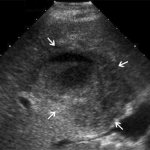

ECG picture of ventricular fibrillation

Ventricular fibrillation is chaotic, ineffective contractions of the heart muscle that occur as complications of diseases of the cardiovascular system, as well as due to electrical trauma, wounds to the heart, drug and drug poisoning. On an ECG, this condition is recorded as a sinusoidal curve. In 80% of cases, sudden cardiac arrest is caused by this.